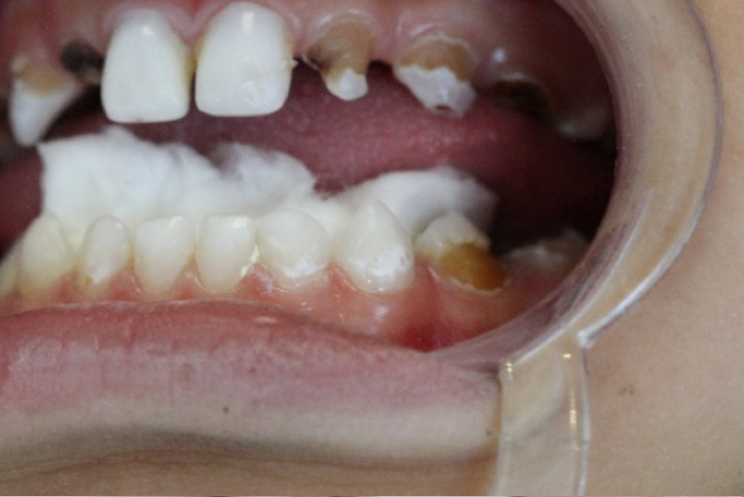

Paciente do sexo masculino, 7 anos de idade, compareceu ao consultório acompanhado pela mãe que se queixava de muitas lesões de cárie nos dentes de seu filho. Após anamnese, exame clínico observou-se presença de lesões de mancha branca nos elementos 72 e 73. (foto 1 e 2)

Para a resolução do caso foi proposta paralisação das lesões com Riva Star. (foto 3, 4 e 5)